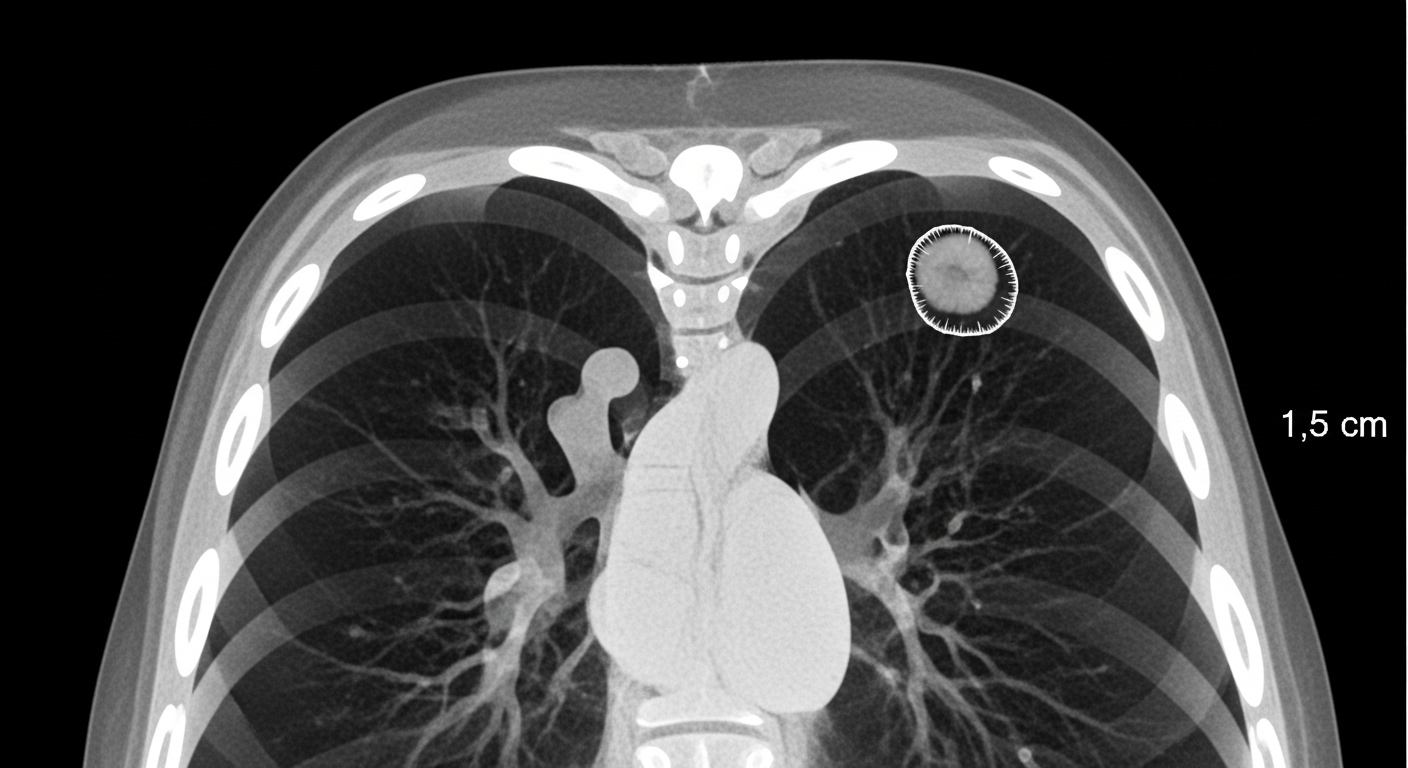

폐결절은 폐 내부에 생긴 지름 3cm 이하의 고립된 음영(덩어리)을 말합니다.

CT나 X-ray 검사에서 작은 동그라미처럼 보이며, 보통은 증상이 없습니다.

모양, 경계, 음영 정도에 따라 '고형 결절', '유리음영(GGO)', '부분 고형' 등으로 분류됩니다.

- 저선량 흉부 CT – 결절의 크기, 경계, 형태 정밀 확인